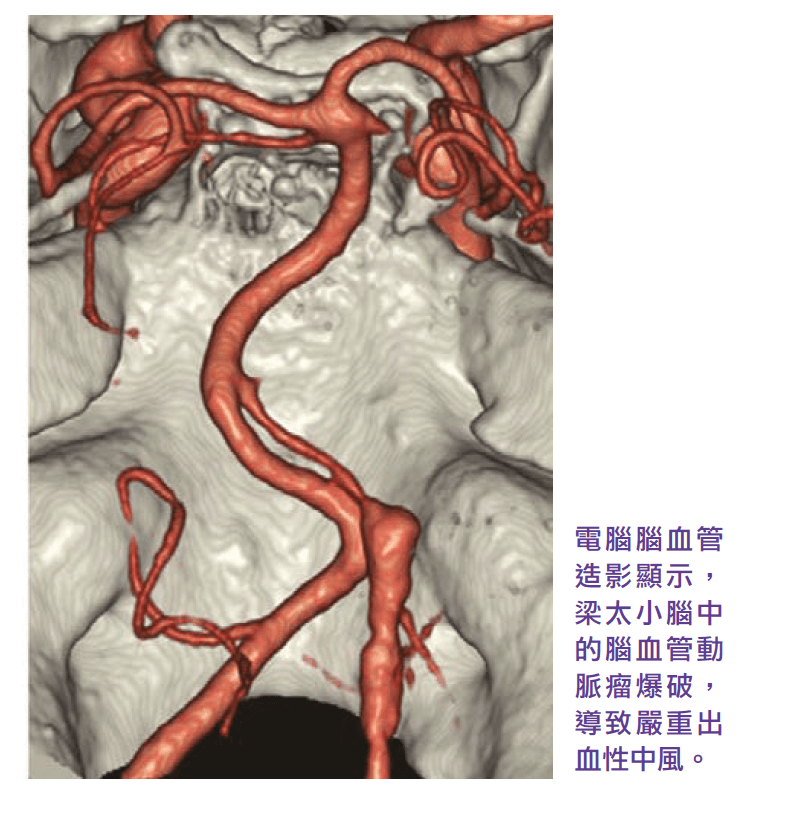

Three years ago, a 46-year-old Ms Leung, has headaches for three or four weeks, consulted his family doctor when arrived at the emergency room, the symptoms disappeared after taking the medication. Later, the brain CT scan report from the public hospital no abnormal finding. so the patient and her family thought that everything was fine. Two weeks later, suddenly felt a severe headache at home and quickly fell unconscious. After emergency treatment in a public hospital, CT scans and cerebral angiography showed that Ms. Leung’s cerebellum had suffered a severe hemorrhagic stroke due to the rupture of a cerebrovascular aneurysm, and that a blood clot in the cerebellum pressed against the brainstem, resulting in hydrocephalus and high intracranial pressure and dilated pupils. A neurosurgeons need to clip the blasted cerebrovascular aneurysm, remove blood clots from the cerebellum, and drain the ventricles through emergency craniotomy to reduce the pressure on the compressed brainstem and intracranial pressure.